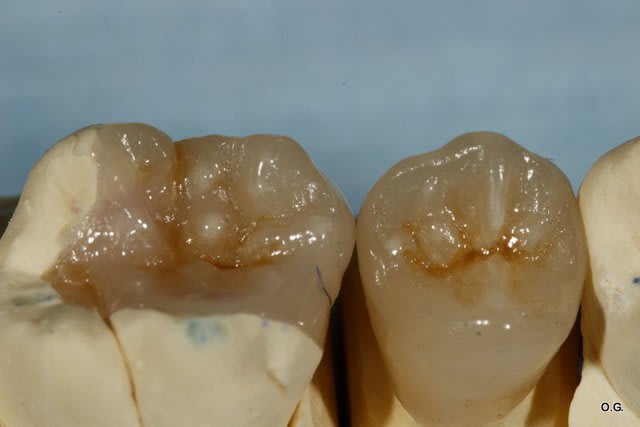

Bonjour que feriez vous sur cette 46 qui a été dépulpée correctement.

La patiente a 10 ans.

Voici un exemple d'onlay sur dent dévitalisée.

Tes photos sont superbes Cingulum.

Maintenant j'avoue que je n'oserais pas faire qu'un simple inlay/onlay.

Le fait qu'une des faces proximales soit effondrée diminue considérablement la résistance mécanique de la dent (enfin c'est ce qu'on m'a appris).

Sur le cas que je viens de poster, l'amalgame date pas d'hier, et il est pas top.. pourtant la dent est pas cassée, et pourtant dévitalisée ... pourquoi ?

Car pas de récidive de carie, et surtout les structures restantes s'assument...

L'onlay collé, fera mieux que ce plombage.